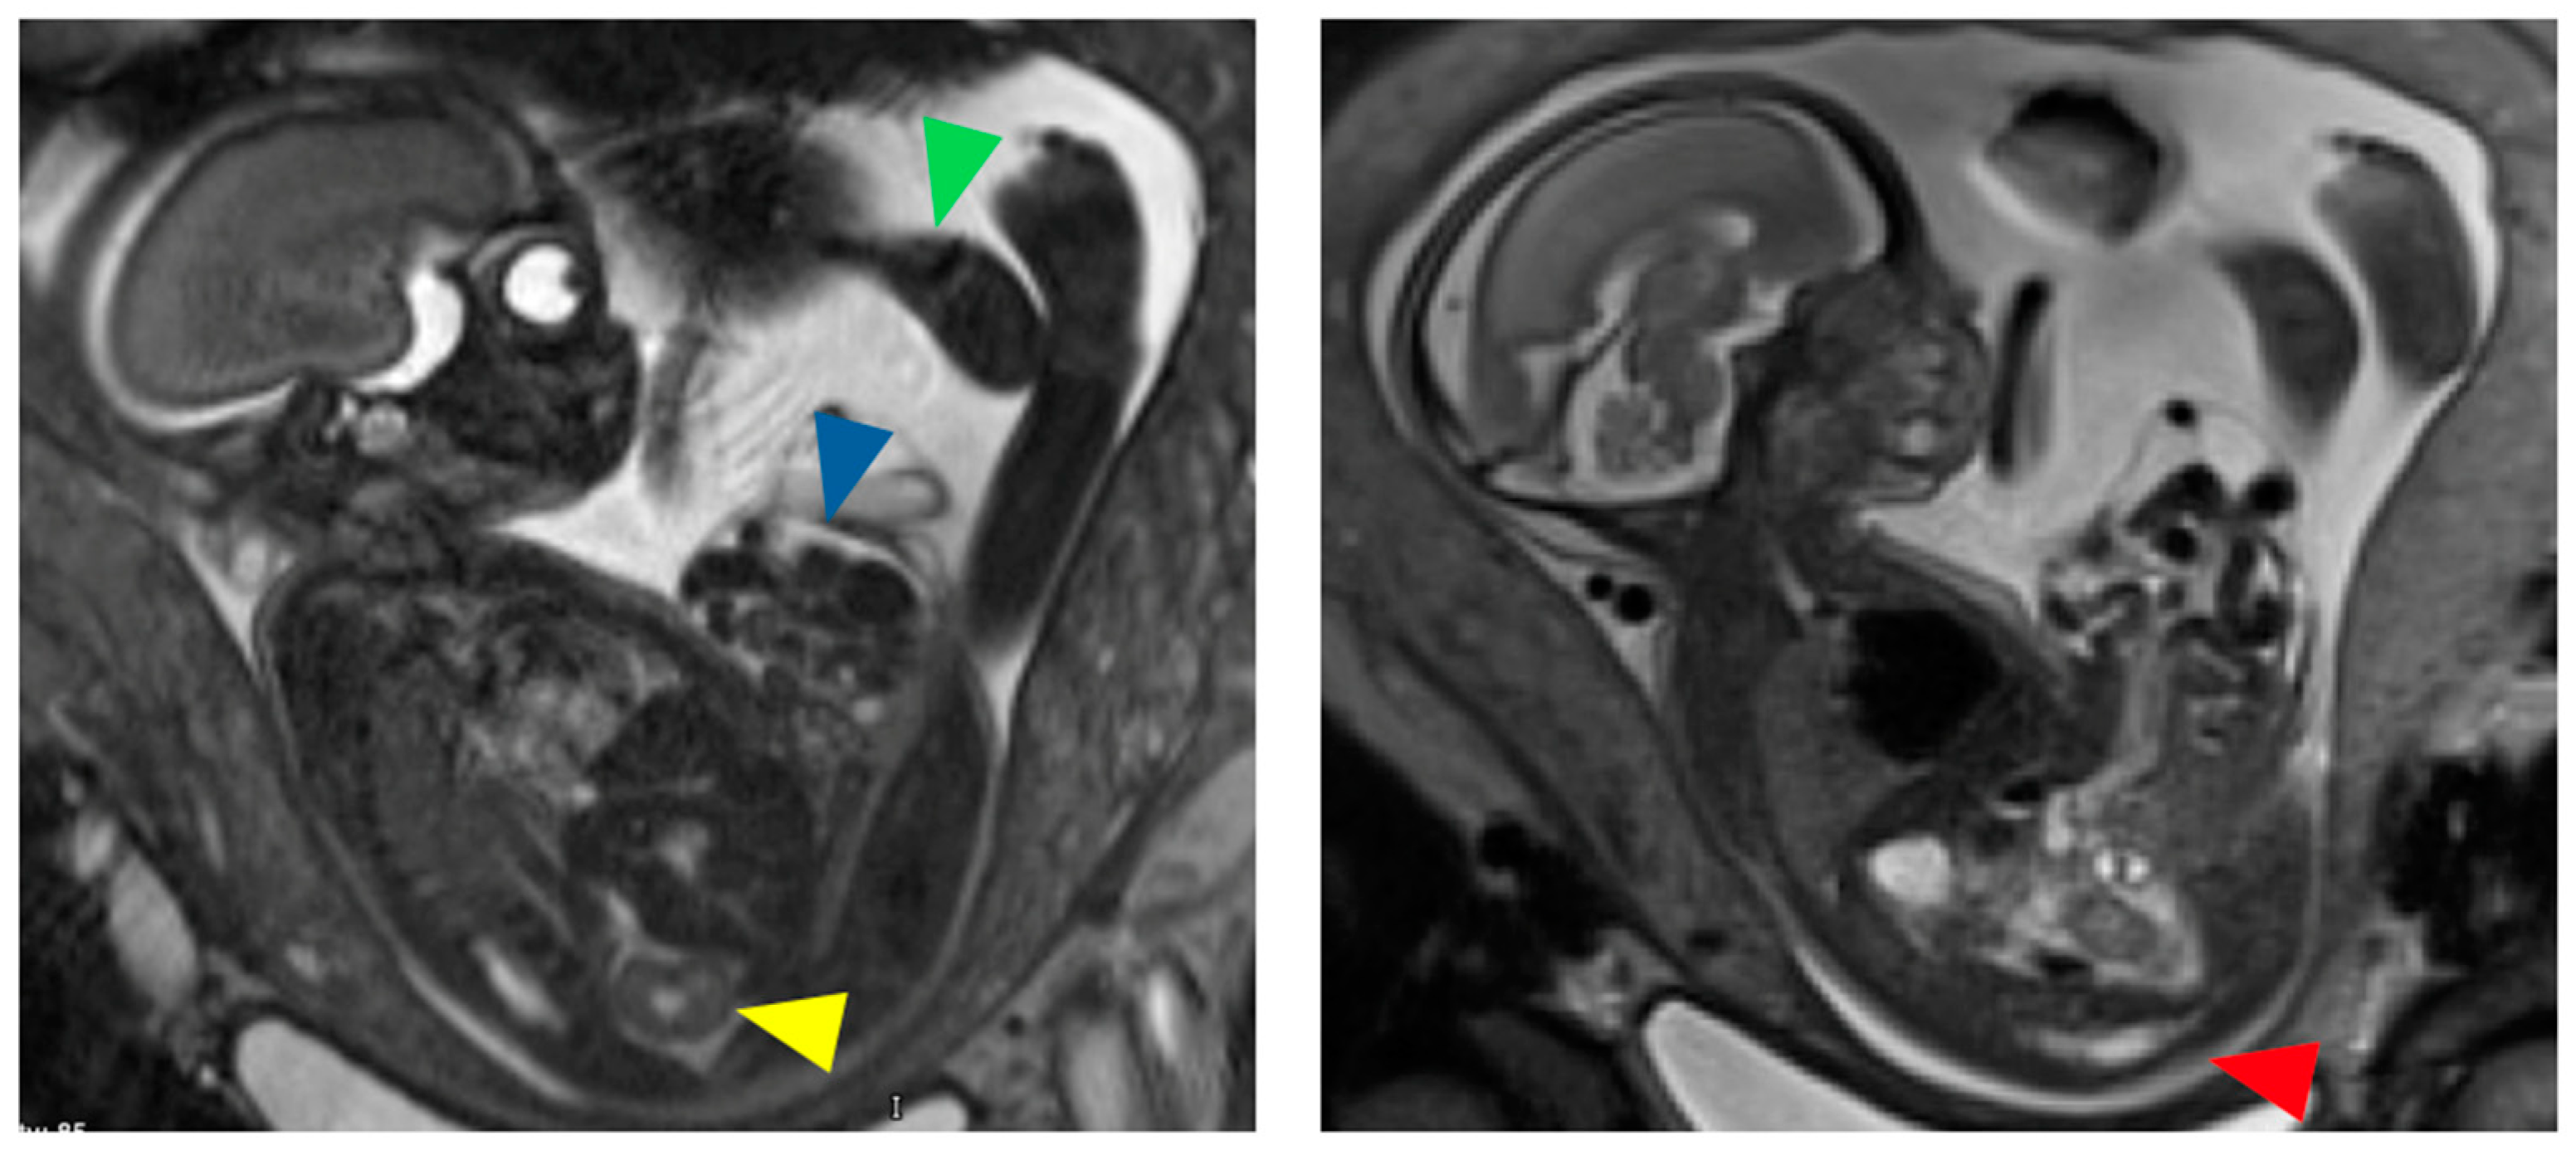

Figure 1.

Fetal MRI images of a female fetus at 24 weeks gestation with characteristic findings of cloacal exstrophy including large omphalocele (blue arrow), absent urinary bladder, right pelvic kidney with absent left kidney (yellow arrow), left club foot (green arrow), and low spinal cord termination with truncated sacrum and coccyx (red arrow).